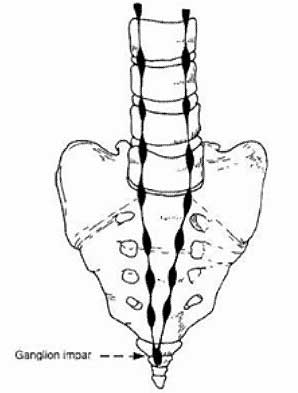

Ganglion van Impar

= Dit is het meest caudale (= naar het staartbeen gelegen) ganglion van het sympathisch zenuwstelsel dat gelegen is tegen de binnenzijde van het heiligbeen en dat vaak een rol speelt bij pijn t.h.v. het staartbeen en rond de anus

De patiënt moet in buiklig op de behandeltafel gaan liggen. Wanneer de patiënt onder narcose is, zal de arts de naald tot tegen het ganglion van Impar brengen. Hiervoor prikt de arts de naald door het sacro-coccygeaal ligament (= ligament tussen heiligbeen en staartbeen). De arts kontroleert door middel van röntgenstralen en toediening van kontraststof de juiste ligging van de naald voordat het lokaal verdovend middel, het corticoïdpreparaat of de neurolytische oplossing wordt geïnjekteerd.